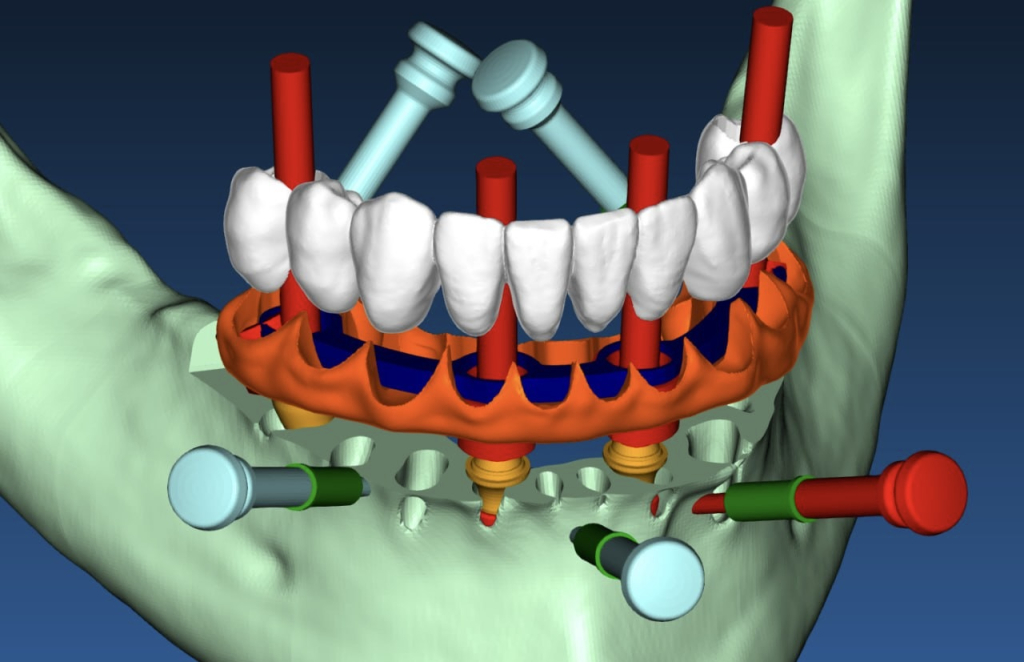

Работа со статической системой начинается с компьютерного моделирования. Для создания виртуального шаблона используют координаты будущих имплантатов (данные пространственного позиционирования). Программное обеспечение, например, интегрированное в coDiagnostiX, генерирует файл в специальном формате для экспорта на устройство трёхмерной печати.

Ключевой этап — перенос цифрового плана в физический шаблон. Рентгенологический шаблон крепится к пластине Templix тремя контрольными штифтами. Устройство GonyX считывает их положение для точной пространственной привязки и переноса данных. После импорта файлов DICOM в ПО для планирования программа создаёт проект для изготовления шаблона. Гипсовая модель и рентгенологический шаблон помещаются в аппарат GonyX с использованием бумажного контрольного шаблона для ориентации.

Координаты каждого имплантата импортируются в GonyX, где для их точного определения используются четыре круговые штифтовые шкалы (обозначаемые А, В, С и D). На основе этих данных аппарат автоматически сверлит в шаблоне точные отверстия под направляющие втулки.